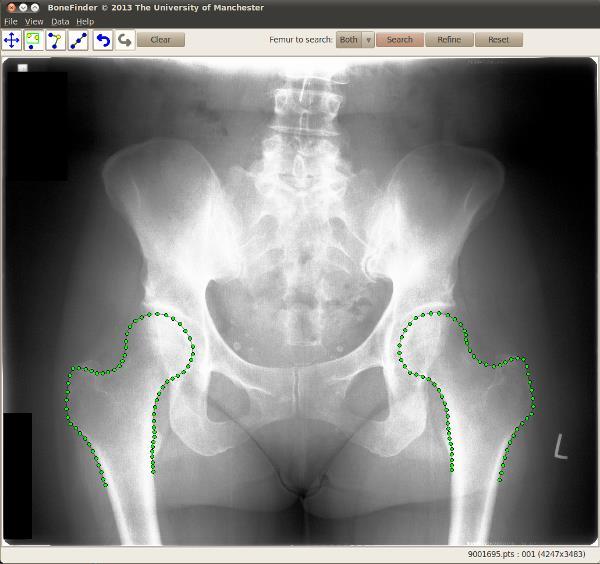

Amidst a national shortage of radiographers in the UK and an increasing requirement for researchers to work with large databases of radiograph images, the software which is being funded by the Engineering and Physical Sciences Research Council, is being designed to automatically pick out the shapes of bones in the images, rather than relying on individual researchers.

The system can already identify hips, but the researchers from the University's Institute of Population Health will now adapt it to map out knees and hands and to be able to learn to identify other bones and structures within the body.

The funding of £300,000 lasts for three years and builds on earlier work which developed software, called Bonefinder, to identify problems and find the outlines of hips. This free software has been adopted by a number of research groups, including some based in Oxford and California.